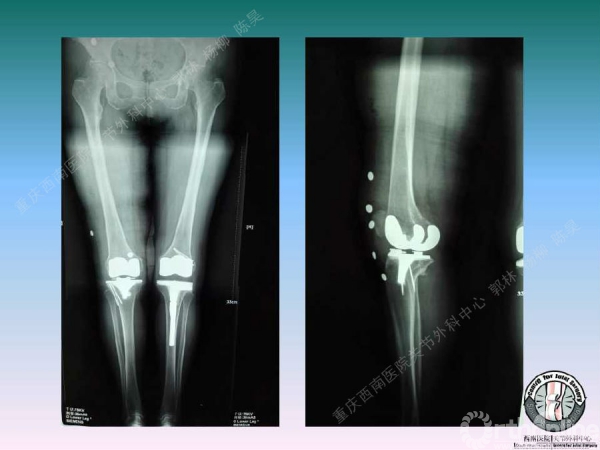

导读:文中,来自重庆西南医院的郭林教授为大家介绍了股骨冠状位关节外畸形的TKA的相关知识,并详细阐述了关节外畸形的概念、诊断、关节内滑移截骨技术等相关内容。

滑移截骨纠正关节外畸形